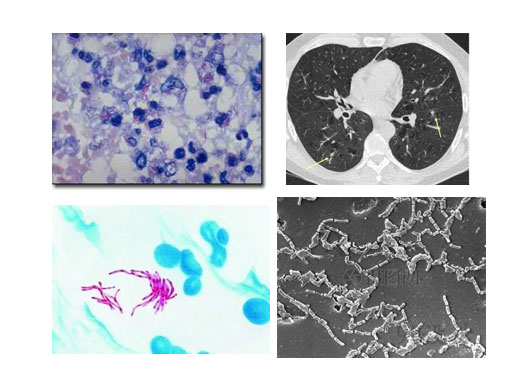

非结核分枝杆菌诊疗

我科也致力于非结核分枝杆菌的诊断与治疗。我们拥有先进的分枝杆菌菌种鉴定技术及NGS技术,能够精确到非结核分枝杆菌菌种,并能够进行体外药敏试验,为患者制定个体化治疗方案。